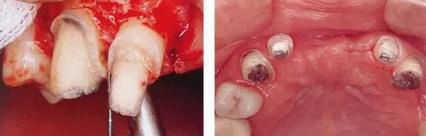

360截圖20170422101910161.jpg

▲圖7-1

對上頜前牙進行初期治療后的咬合面觀。右上2,3存在炎癥。

360截圖20170422101920025.jpg

▲圖7-2,3

▲圖7-2 齦瓣剝離后,可以看到右上3近中側(cè)沉積著大量牙結(jié)石。由于牙根接近而無法用刮匙除去

▲圖7-3  牙周外科處理后的愈合期狀態(tài)。右上2,3之間愈合形成了充分的角化齦。